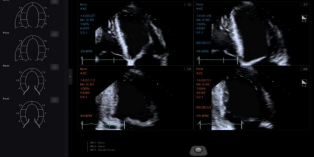

Stress Echo 负荷成像

‒ 提供心电图触发采集、显示,选择比较、评估和在不同阶段的多个心脏节段动态图存档的负荷超声检查

‒ 简化整个检查流程

‒ 室壁运动评分:16/17 节段模型与图形显示和左心室(LV)体积测量与报告打印